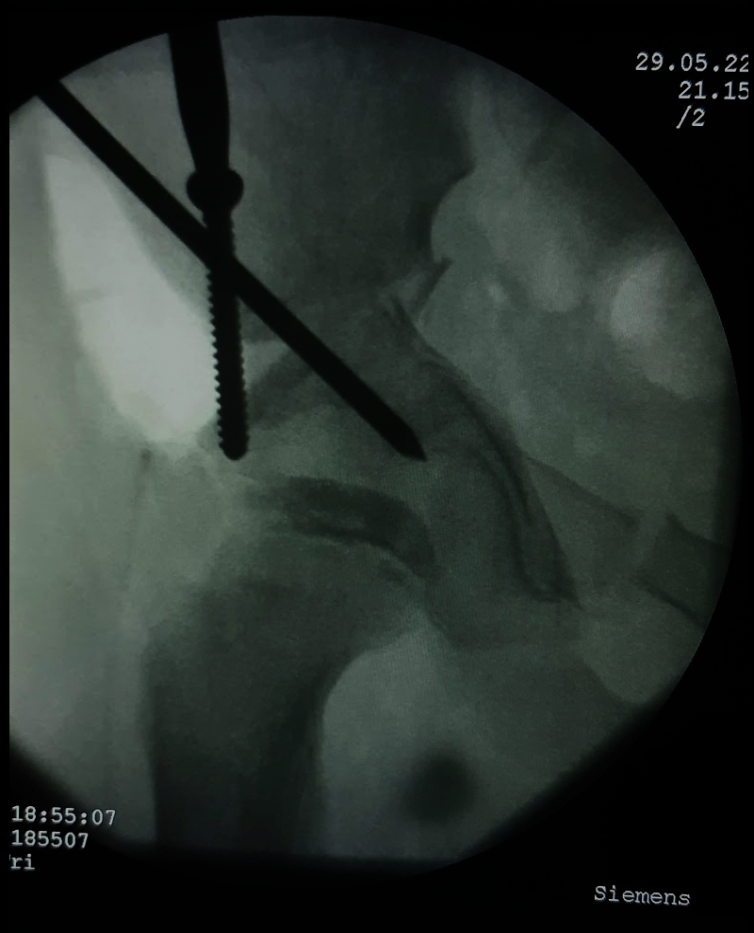

Hình ảnh bệnh nhân được đục xương ổ cối và chỉnh xoay (Nguồn: BVĐK tỉnh Quảng Trị)